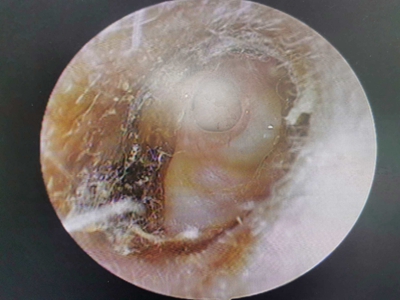

霉菌性外耳道炎外耳道有白粉末里边有肉赘图

霉菌性外耳道炎患者外耳道边缘有大量的白色鳞屑,融合呈团片状,形状不规则,境界清楚,同时在外耳道深处有乳头状肉赘,外观类似小葡萄。